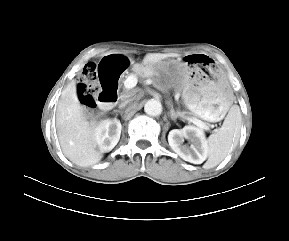

标题: CT19533:病变来源于哪?

患者,男,发现上腹部包块两月余。

病变位于肝胃间隙,实际就是位于小网膜囊(左肝下后间隙),呈轻度不均匀性强化,腹腔内及腹膜后见多发肿大淋巴结。所以我考虑肝胃间隙恶性胃肠间质瘤并淋巴结转移。

病灶强化不显著,灶周及腹膜后见多量淋巴结肿大,考虑淋巴瘤可能,其次考虑间质瘤

病灶与胰腺分界不清,来源于胰腺?

强化后病变与胃壁分界清楚,并且血供不是来源胃壁血管。考虑胰腺颈体癌并腹腔腹膜后淋巴结转移。